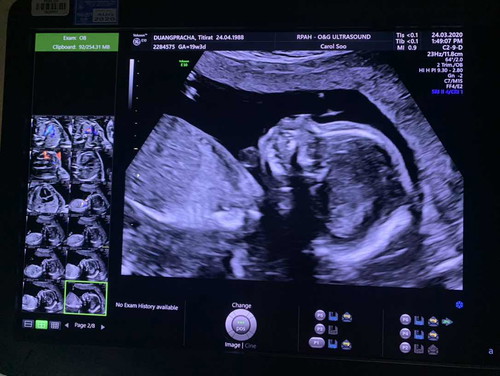

วันนี้ไปอัลตราซาวด์มาค่ะ ที่รพ.ให้หยิบบัตรคิวเองและให้นั่งห่างกัน 1.5 เมตร ก่อนเข้าห้องซาวน์ เจ้าหน้าที่แจ้งว่าเข้าได้คนเดียวคือคุณแม่ ส่วนคุณพ่อต้องไปรอข้างนอก เพราะเค้าจำกัดพื้นที่และเป็นห่วงการติดเชื้อ เพิ่งมีกฏมาใหม่วันนี้คุณพ่อเลยอดเข้าไปลุ้นเพศลูกเลย ผลออกมาได้ลูกสาวค่ะ 19w3d ค่ะ มาเกิดช่วงนี้คุณแม่และคุณลูกต้องสตองเป็น 2 เท่า แล้วเราจะผ่านช่วงเวลานี้ไปด้วยกันค่ะ ?